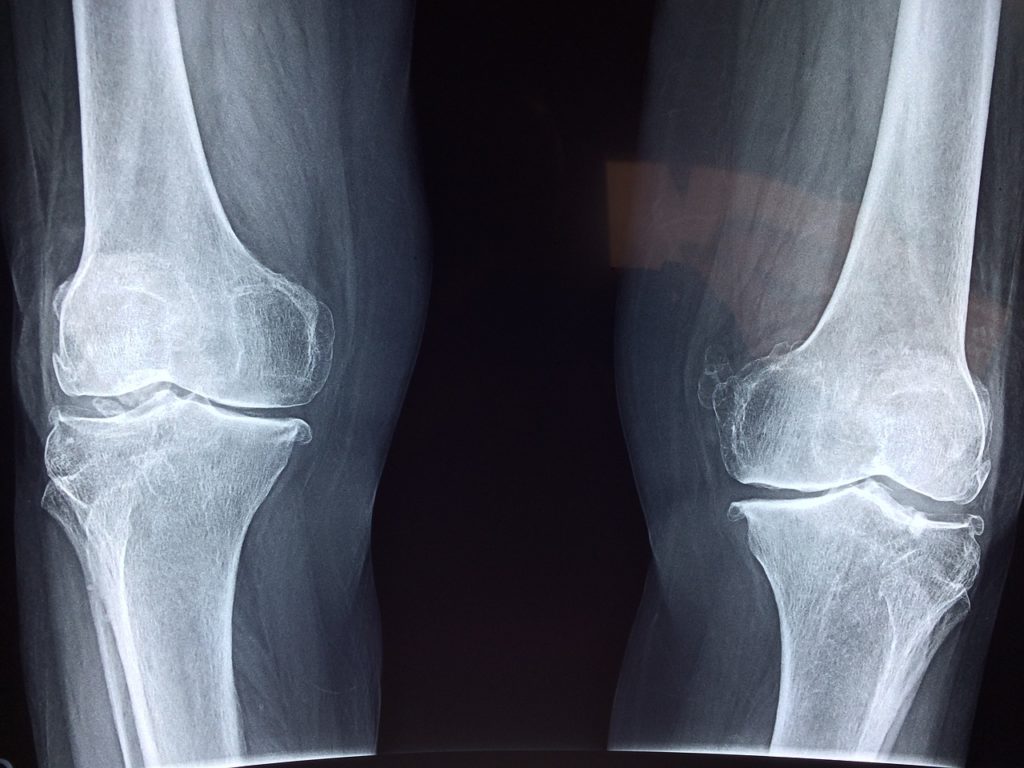

Bóle kości, stawów czy kręgosłupa potrafią bardzo uprzykrzyć życie.

Osoba ma ograniczone możliwości poruszania się, a ból może ją dosłownie sparaliżować. Nie czekaj na cud i wypróbuj tę skuteczną naturalną mieszankę, która może przynieść upragnioną ulgę.